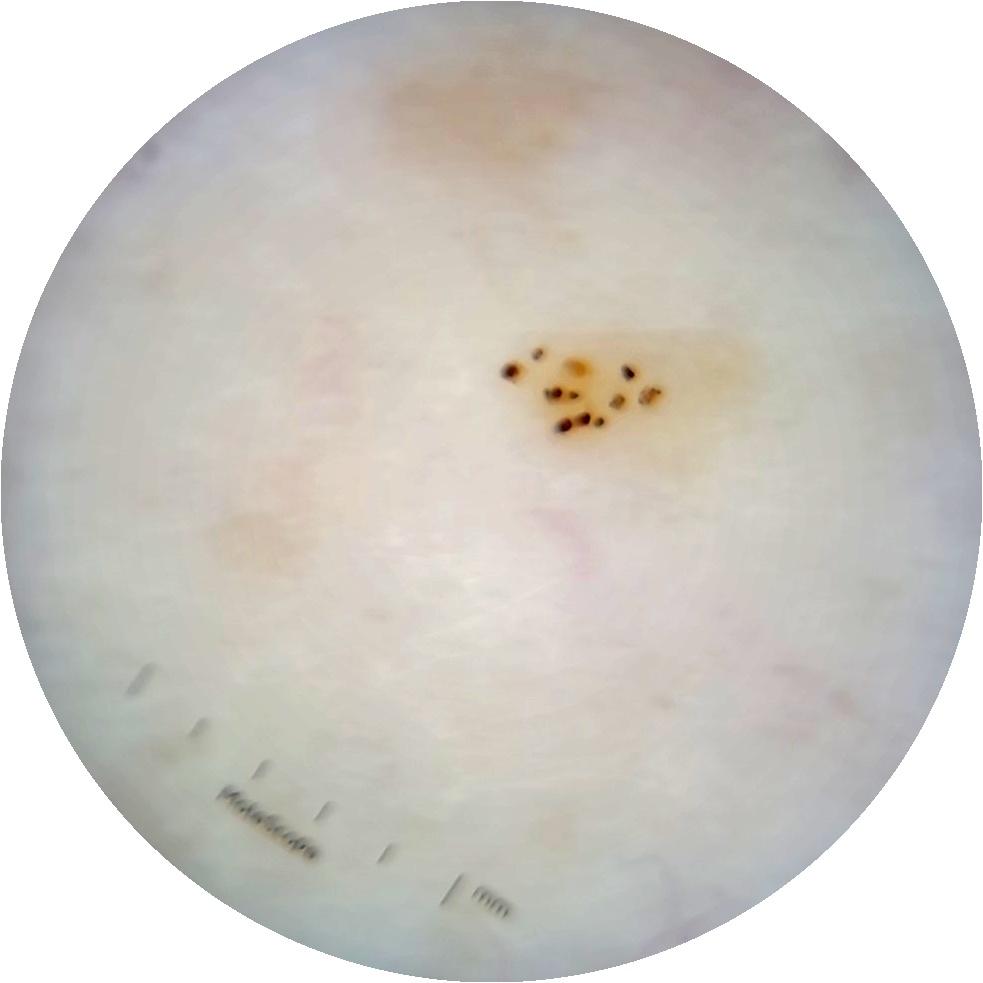

ISIC_6363669

MEL-SELF Trial, https://www.sydney.edu.au/medicine-health/our-research/research-centres/melself-project.html

Clinical

Field Value

acquisition_day 264

age_approx 65

anatom_site_1 Trunk

anatom_site_2 Anterior trunk

anatom_site_general anterior torso

concomitant_biopsy False

diagnosis_1 Benign

diagnosis_confirm_type single image expert consensus

family_hx_mm True

image_manipulation instrument only

image_type dermoscopic

lesion_id IL_2591344

patient_id IP_1322385

personal_hx_mm True

sex female